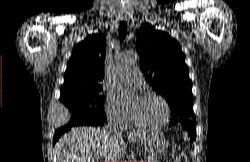

Пациент 1946 г.р., состоит на Д учете в онкодиспансере по поводу с-ч кожи (базалиома), прошел курс лучевой терапии, в 2009г на Ргенографии выявили образование 7 ребра, направили на Кт, на КТ (2009г) был выставлен д-з ГКО, пункционная биопсия не произведена. А сейчас вот такая картина, с множественными литическими очагами в костях грудного склета + образование 7 ребра, с отрицательной динамикой.

повторно взяли пациента, сняли кости таза, такая же картина- множественные очаги литической деструкции. Заключение: больше данных за миеломную болезнь.